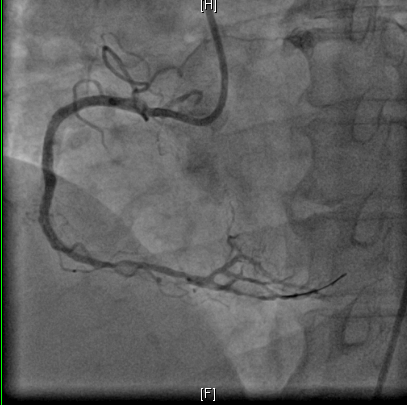

图2 应用RASER技术治疗术前及术后的冠脉造影结果对比

准分子激光根据病变性质,选择合适的能量密度及脉冲频率,在这个病例中采用能量45mJ/mm²、频率40Hz共消蚀3次,球囊仍无法通过病变,随即换用旋磨导丝顺利通过病变并应用1.25mm磨头完成两次旋磨后,顺利完成球囊扩张及再次植入1枚支架,最终应用血管内超声(IVUS)精准评估手术后效果。